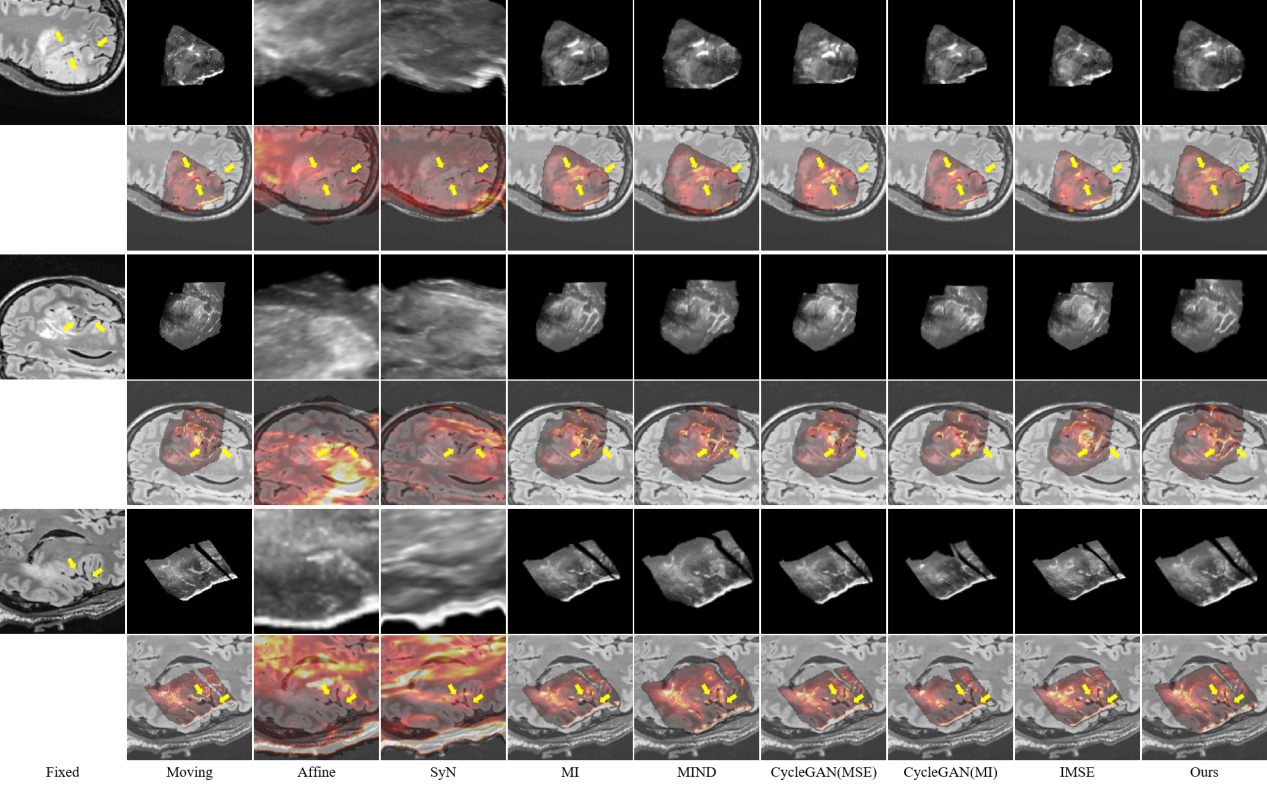

研究结果表明,SynMSE 在L2R 2022 CT-MR腹部数据集、临床宫颈CT-MR数据集以及CuRIOUS MR-US脑数据集上均取得了最优配准性能。与传统方法相比,SynMSE显著提升了Dice系数、降低了HD95与TRE误差,实现了在复杂模态差异下的高精度解剖结构对齐。图4-图6分别为所提出方法在三个数据集上的定性结果展示,红色标注代表固定图像的目标器官区域,黄色标注代表浮动图像与配准后图像的目标器官区域。表示图中结果显示,SynMSE更好的克服了多模态图像间的复杂分布差异,不仅实现了更精确的配准效果,而且有效保持了组织边界与解剖拓扑的完整性,明显优于现有方法。

图4:所提出方法与现有方法在L2R 2022 CT-MR腹部数据集上的定性效果

图5:所提出方法与现有方法在临床宫颈CT-MR数据集上的定性效果

图6:所提出方法与现有方法在CuRIOUS MR-US脑数据集上的定性效果(黄色箭头指向图像上的较为明显的脑沟等显著结构